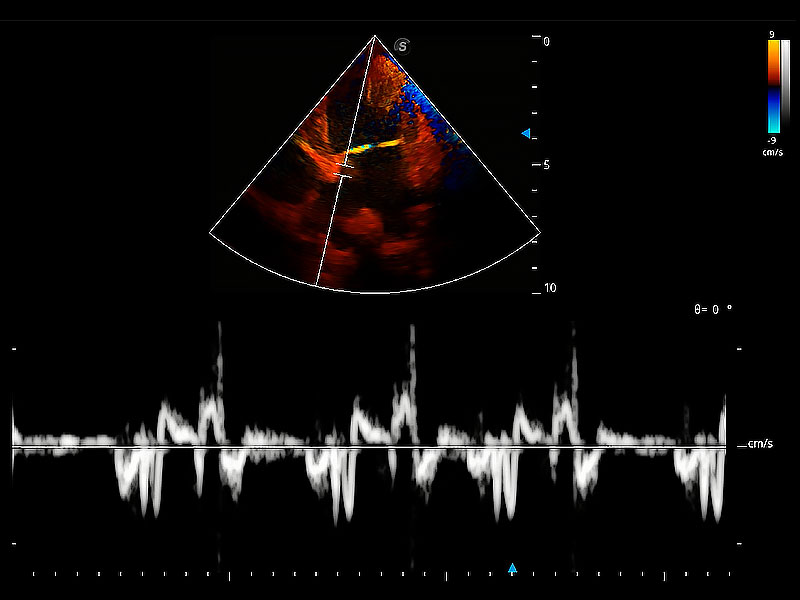

ProPet 80 配備了豐富的心臟探頭群、先進(jìn)的成像技術(shù)和專業(yè)的心臟測量工具,可幫助動物醫(yī)生為不同體型和生理結(jié)構(gòu)的動物提供心臟和心肌功能的全面評估。

實(shí)時用顏色表示心肌組織運(yùn)動,觀察和定量組織的運(yùn)動情況,對快速檢測與評估心肌的灌注和活性、電傳導(dǎo)及心肌收縮和舒張功能等均能提供重要的診斷信息。